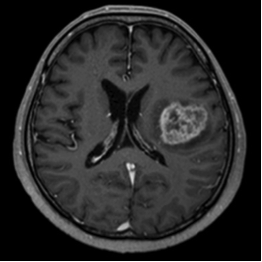

3.転移性脳腫瘍

脳腫瘍の中で最も多い腫瘍です。1個の単発こともありますが、多い時には100個くらい見つかることもあります。手術して摘出する場合もありますが、ほとんどはサイバーナイフ・トモセラピーによる定位放射線治療で治療します。手術と放射線治療の両方を行うこともあります。癌の種類によっては化学療法が有効の場合もあります。定位放射線治療による治療効果は、消失約10%、縮小約80%で、きわめて有効です。手術・定位放射線治療のいずれも困難な場合は、全脳照射を行います。

トモセラピー前